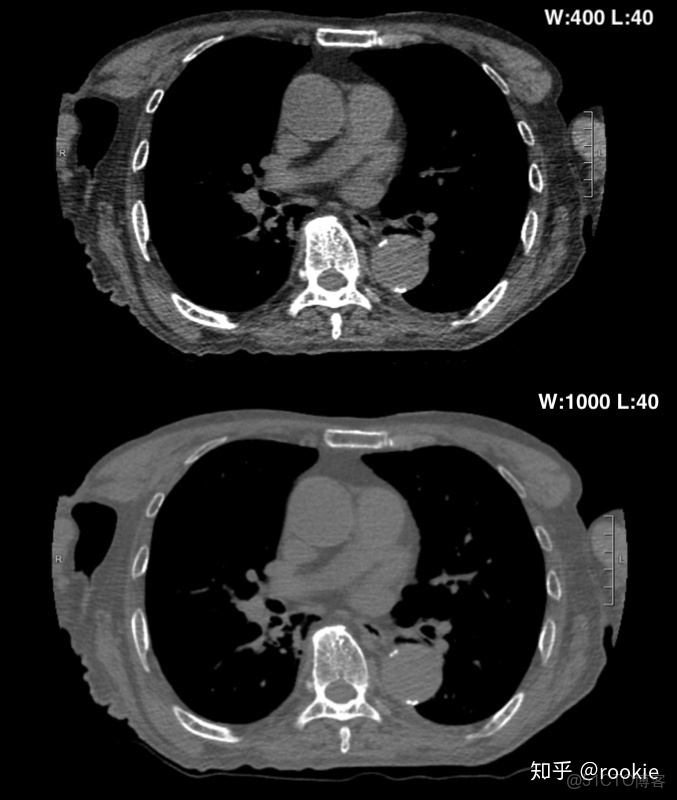

調整窗口寬度:增大窗口寬度將降低圖像的對比度:隨着窗口寬度的增加,將需要更大的密度變化來改變代表某個HU單位的灰色陰影。由於更多的結構看起來相似(儘管密度不同),因此會導致對比度下降。減小窗口寬度將增加 圖像的對比度: 隨着窗口寬度的減小,密度的較小變化將導致研究圖像的顏色發生變化。由於密度接近的結構將具有不同的灰色/白色/黑色陰影,因此將提供更高的對比度。

CLAHE算法增強局部對比度的X光圖像增強效果對比_f5_06

上面的圖像顯示了增加窗口寬度將如何降低圖像的對比度。與下窗格相比,頂部窗格的窗口寬度更小,皮下組織中的肌肉和脂肪之間的對比更加明顯。